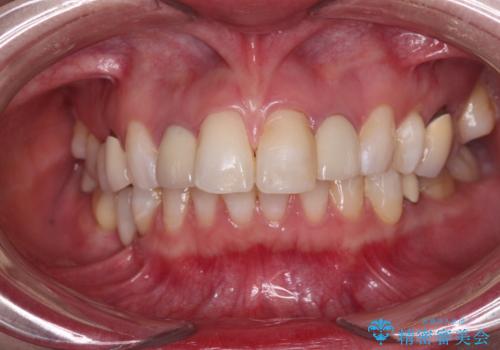

- クラウンから金属の土台が見えてきてしまったとのことで、作り替えを希望して来院された患者様です。

前歯や金属が露出している歯、痛みを感じる歯を中心に、オールセラミッククラウンにて補綴治療することとしました。